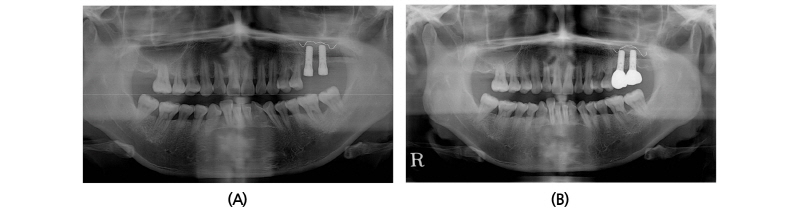

A 45-year old female patient who had missing teeth of first (#26) and second molar (#27) in left maxilla visited the clinic to plan for the reconstruction of both molars (Fig. 1). The edentulous ridge had sufficient buccopalatal width and the vertical dimension was about 8 mm from the soft tissue level (Fig. 1A, 1B). The patient was diagnosed as generalized chronic moderate periodontitis and received nonsurgical periodontal treatment prior to the surgery. In addition, regenerative therapy using bone graft materials was prepared in the intrabony defect of right mandibular first molar (#46). The missing maxillary molars were decided to be placed with implants and the panoramic view showed deficient RBH at #26 and #27 with sinus pneumatization (Fig. 1C). In computed tomography, RBH at #26 and #27 was measured to be 5 mm and 6 mm, respectively, and SFE spontaneously with implant placement using hybrid technique was planned (Fig. 2). Flap including the midcrestal incision and vertical incision at #25 distal line angle was reflected (Fig. 3A), and linear osteotomy was prepared with a piezoelectric device (Piezosurgery®, Mectron, Carasco, Italy) (Fig. 3B). Mesiodistal width of the osteotomy was about 10 mm to include both implantation site planned for #26 and #27, and was positioned about 7~8 mm from the crest paralleled along the sinus floor. Detachment of the Schneiderian membrane was limited in the internal surface of the floor and a serial drilling one step before the final diameter was done under the protection of the membrane with the sinus elevator inserted through the linear osteotomy site (Fig. 3C). Biphasic calcium phosphate (MBCP®, Biomatlante, Vigneux de Bretagne, France) of 0.5 g was grafted via lateral opening and pushed into the floor with osteotomes and final drilling was done. Straumann SLA® (Institute Straumann AG, Waldenburg, Switzerland) diameter 4.8 RN and 10 mm length implant was installed at both #26 and #27 (Fig. 3D). Non-submerged healing with healing abutment connection was done (Fig. 3E) and the stitches were removed after 10 days (Fig. 3F). Dome-shaped radiopacity surrounding the implant apex penetrated into the floor was shown immediately after the surgery (Fig. 4A) and the prosthetic delivery was done within 3 months of healing periods. Augmented sinus floor was maintained through the 6-year of follow-up (Fig. 4B).

A 40-year old male patient who had missing tooth of first molar at right maxilla (#16) and discomfort of chewing in both posterior teeth visited the clinic for the periodontal treatment (Fig. 5A). Vertical tooth mobility was found on right maxillary second (#17), third molars (#18) and left maxillary first molar (#26) with severe bone loss. The patient was diagnosed as generalized chronic advanced periodontitis and #17, 18, 26 and 28 teeth were planned to be extracted. Nonsurgical periodontal treatment in whole mouth and periodontal surgeries at both mandibular posterior teeth were done. After 3 months of healing in the right maxillary edentulous area, sufficient buccopalatal width and vertical dimension about 12 mm from the soft tissue level was shown (Fig. 5B, 5C). Computed tomography revealed deficiency in the RBH with pneumatized sinus floor and horizontal bone loss especially in #17 site (Fig. 6A), which was measured to be 5 mm (Fig. 6B). The RBH of #16 sites was about 7 mm and spontaneous SFE with implant installation in both #16 and #17 using hybrid technique was planned. After flap reflection, a linear osteotomy at the lateral wall was prepared using piezoelectric device (Fig. 7A). Mesiodistal dimension of the opening was about 8 mm centered at the #17 site and slightly extended to the #16 site. The osteotomy positioned at 7~8 mm from the crest in #17 area and ran parallel along the sinus floor which had inclination from the #16 site. After detachment of the Schneiderian membrane limited in the floor, a serial drilling one step ahead of the final diameter was done with sinus elevator inserted through the lateral opening (Fig. 7B). MBCP® of 0.5 g was grafted via lateral osteotomy site and through the drilling site using osteotomes. Drilling of the final diameter was prepared and Straumann SLA® diameter 4.8 WN with 10 mm length implant was installed at both #16 and #17 (Fig. 7C). Absorbable collagen sponge (CollaTape®, Zimmer Dental, Carlsbad, CA) was covered on the lateral osteotomy site (Fig. 7D) and non-submerged healing was done (Fig. 7E). Dome-shaped sinus floor augmentation around the implant apex was shown immediately after the surgery (Fig. 8A) and prosthetic delivery was done within 3 months of healing periods. The level of SFE was maintained through 4-year of follow-up (Fig. 8B).